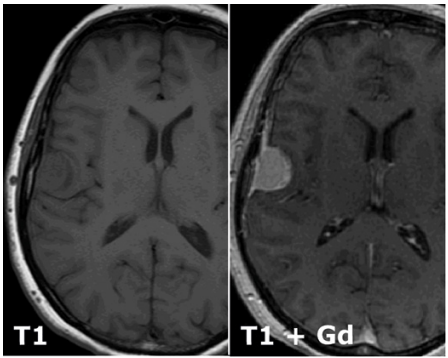

What is a T1 MRI scan and how does it differe from a T2 scan?

T2 is basically T1 but inverted.

T1 shows water dark

T2 shows water bright

Desribe what can be seen. What might it be, and which tissue might it derive from?

A meningioma of the right hemisphere deriving from meningiothelial cells.

Why does gadolinium enhance the lesion?

Gad enchances blood vessels and the tumour will be highly vascular

Which structures in the cerebral hemispehre is the lesion compressing?

The frontal lobe and the primary motor cortex